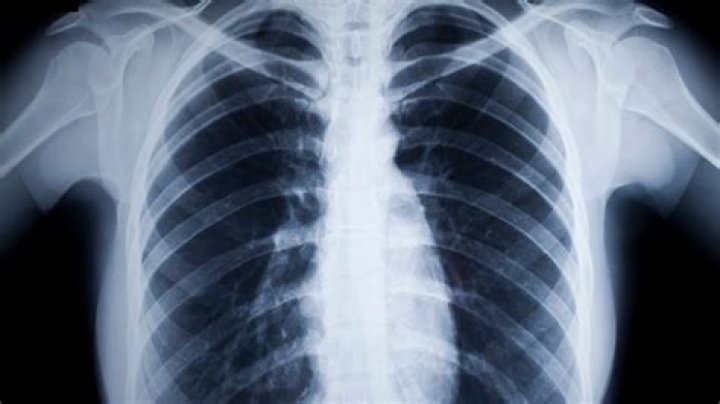

Can an X-Ray Affect My Tattoo? A regular x-ray will not damage your tattoo. A type of imaging called magnetic resonance imaging (MRI) heats up some of the components of tattoo ink.

When being scanned, this metal causes the tattoo to show up as a black spot on the image made by the MRI machine, making it difficult, if not impossible, for the scan to show what is under that part of the skin covered by a tattoo.

Rarely, tattoos or permanent makeup might cause swelling or burning in the affected areas during magnetic resonance imaging (MRI) exams. In some cases, tattoo pigments can interfere with the quality of the image.